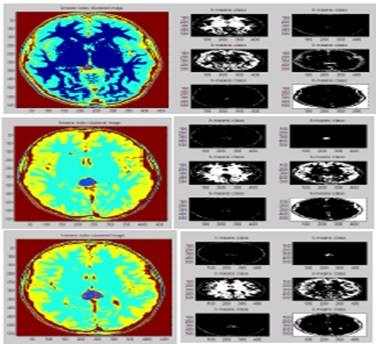

ابتكرت دراسة علمية في كلية العلوم بجامعة بابل,  طريقة جديدة لبناء صور ثلاثية الأبعاد للرنين المغناطيسي في الكشف عن أورام الدماغ.

وبينت الدراسة التي قدمتها الدكتورة رباب سعدون, أن التصوير في الرنين المغناطيسي يمنح وفرة في المعلومات للصور الثلاثية الأبعاد، التي تتعلق بتشريح الأنسجة المرنة في جسم الإنسان، وتعطي تفاصيل دقيقة دون أي تداخل جراحي أو إشعاع مؤين.

وتضمنت الدراسة , استعمال تقنيات معالجة الصور الرقمية المعتمدة على المخطط التكراري لصور الرنين المغناطيسي(MRI ) مع إضافة بعض العمليات المورفولوجية لعزل واستخلاص مناطق الأورام من شرائح صورية متسلسلة لمرضى كانوا يعانون من أورام في الدماغ استعمالها لتوليد الصور الثلاثية الأبعاد.